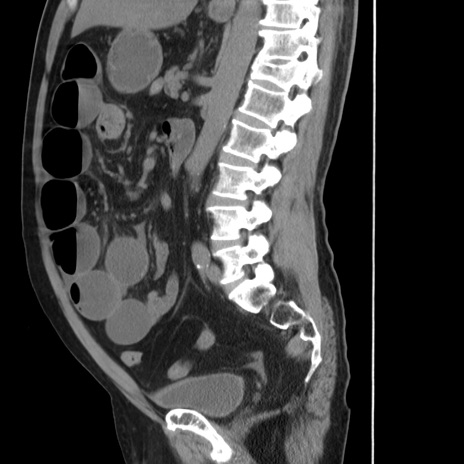

症例20(矢状断像)

【症例】 60歳代男性

【主訴】 腹部膨満、嘔吐

【現病歴】5日前頃より倦怠感を認め食事量減少し4日前の朝嘔吐、食事摂取困難となった。 3日前近医受診し点滴施行され整腸剤などを処方された。 当日他院を受診し、腹部膨満著明、炎症反応の上昇(CRP10.8、WBC11200)あり、紹介受診となる。

【身体所見】 意識JCS1 受け答えがはっきりしないBP 111/57mHg、 P 67bpm、、BT35.2°C、SpO2 97%(RA)、 腹部:膨隆、打診で鼓音あり、全体的に圧痛有り、腸蠕動音(-)、反跳痛ははっきりせず。

【データ】WBC 11400、CRP 14.20